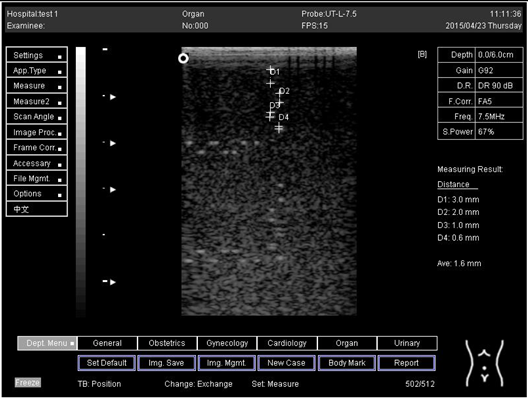

5.0Axial resolution

Biomimetics 07 00130 i011

D1 = 3.0

D2 = 2.0

D3 = 1.0

D4 = 0.5

5.0 Lateral resolution

Biomimetics 07 00130 i012